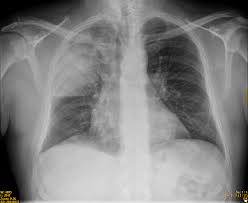

Un ensayo pragmático de glucocorticoides para la neumonía adquirida en la comunidad

En pacientes con neumonía adquirida en la comunidad en un entorno de bajos recursos, la terapia adyuvante con glucocorticoides se asoció con un menor riesgo de muerte que la atención estándar. New England Journal of Medicine, octubre de 2025.